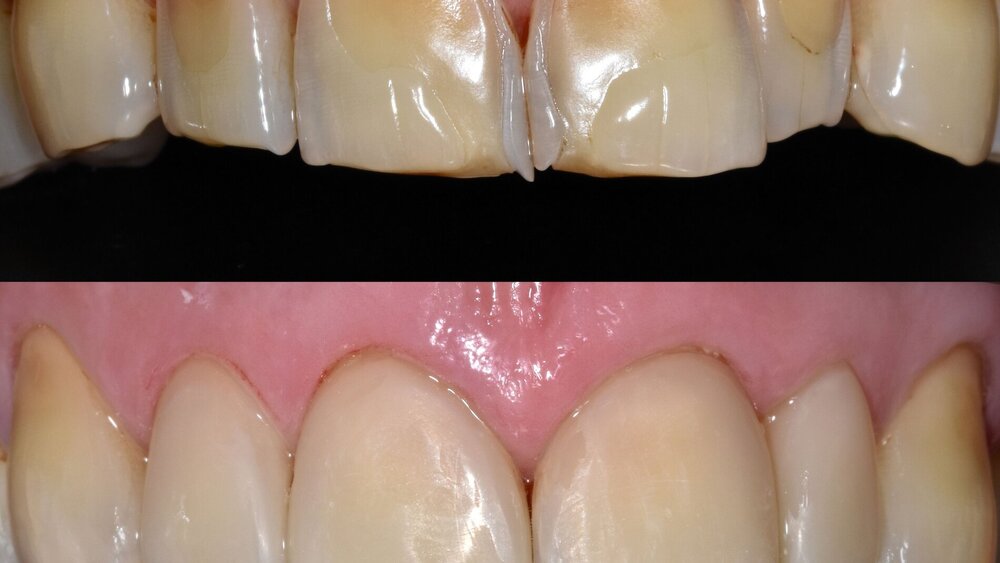

... für Zahnformkorrekturen im Frontzahnbereich

Ähnliche Ergebnisse wurden bei Zahnformkorrekturen erzielt. Die untersuchten Studien berichteten über hohe bis sehr hohe Überlebensraten von Komposit-Restaurationen mit Nachbeobachtungen bis zu 15 Jahren. Beim Vergleich mit indirekten Keramikveneers zeigten diese zwar höhere Überlebensraten, doch basiert diese Schlussfolgerung auf einer einzelnen Studie mit kurzer Nachbeobachtungszeit [Meijering et al., 1998]. Die Nutzen-Schaden-Bewertung spricht klar für den Einsatz von Kompositen zur Zahnformkorrektur im Frontzahnbereich (Abbildung 3), aufgrund der hohen Überlebensraten, der guten bis ausgezeichneten klinischen Qualität, der Reparierbarkeit und der geringeren Invasivität im Vergleich zu Keramikveneers. Der elektive Charakter dieser Verfahren sollte bei der Gesamtbeurteilung berücksichtigt werden. Für diese Behandlungen wird ein minimalinvasiver oder nichtinvasiver und präventionsorientierter Ansatz empfohlen.